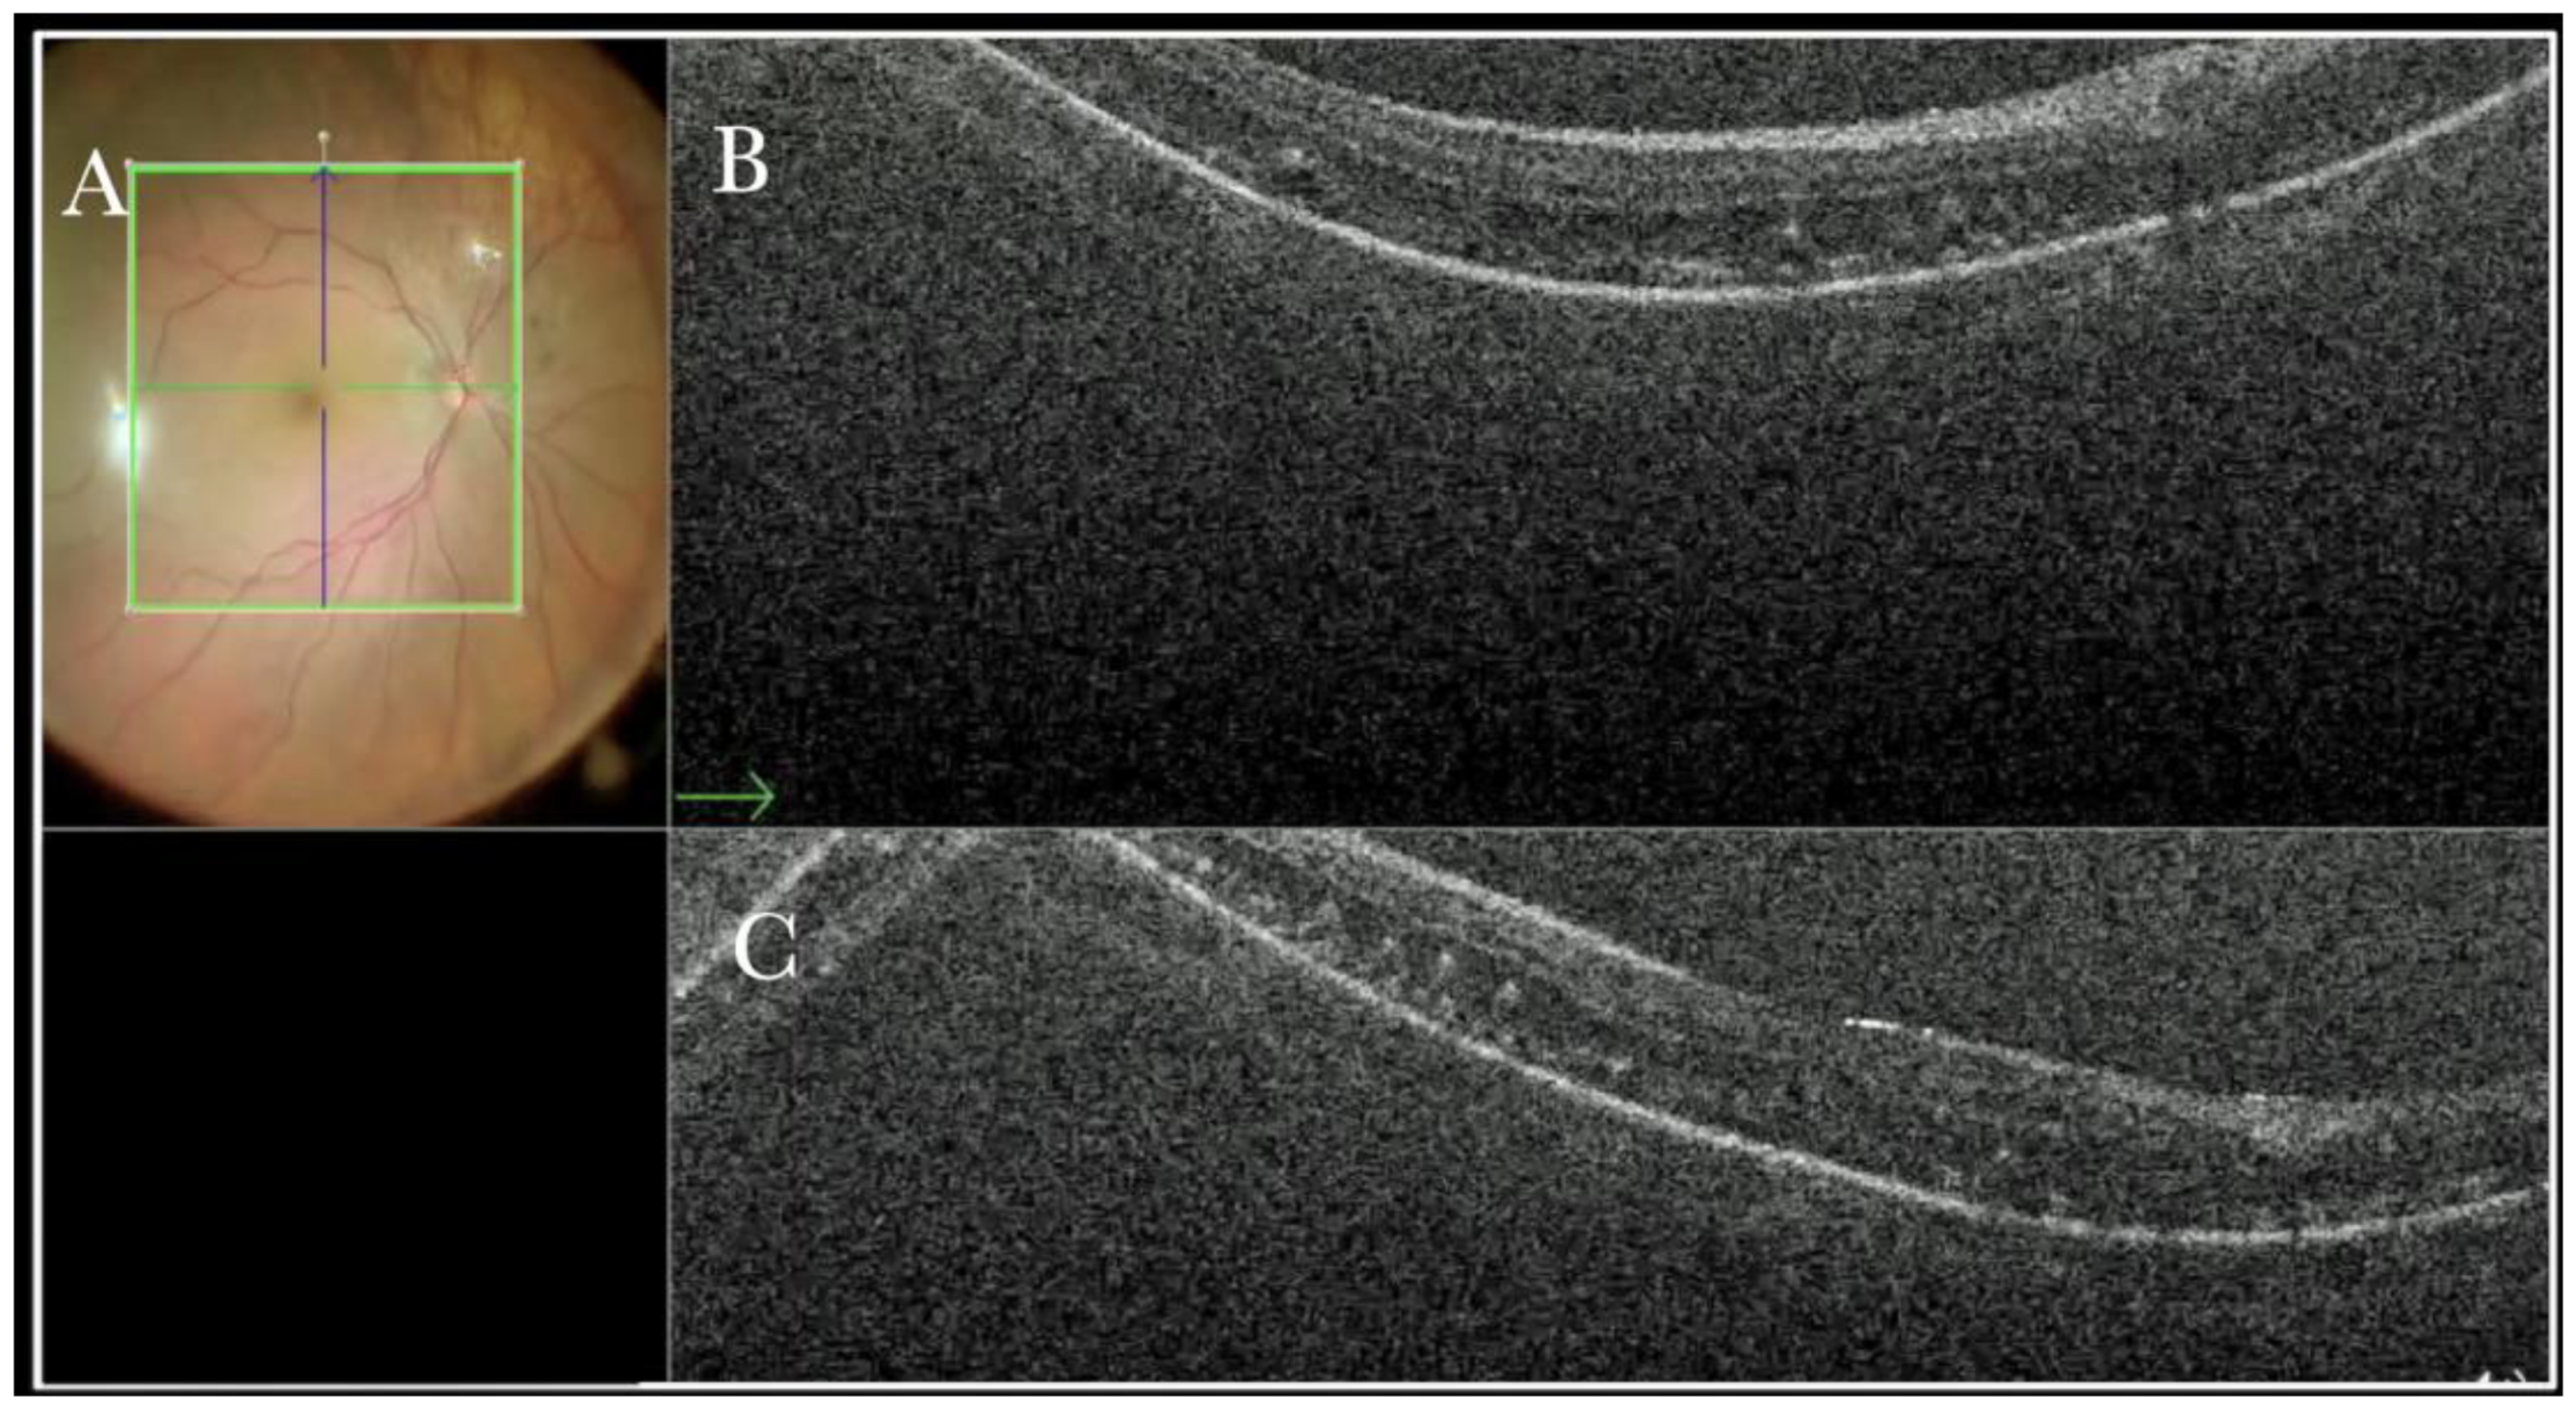

Figure 11.

(A) Microscope view of the macular area in case of myopic traction maculopathy in stage 4C (macular detachment with full-thickness macular hole (FTMH)) after implanting a macular buckle. The transillumination of a fiber optic inserted into the buckle allows us to guess the location of the buckle itself. The inner limiting membrane (ILM) flap is visibly stained blue. The FTMH is not visible. (The white box indicates the field-of-view of the OCT scan, the green line within the green box shows the scan plane) (B) The Intraoperative Optical coherence tomography (i-OCT) B horizontal (green arrow) and vertical scan shows very clearly the indentation of the macula from the scleral side due to the presence of a macular buckle. The white arrowhead shows the FTMH, which is not over the buckle. (C) Same view as in A after repositioning the macular buckle. (The white box indicates the field-of-view of the OCT scan, the green line within the green box shows the scan plane) (D) i-OCT B horizontal (green arrow) and vertical scan showing very clearly the indentation of the macula from the scleral side due to the presence of a macular buckle. The white arrow shows the FTMH, which is now well-positioned over the buckle.